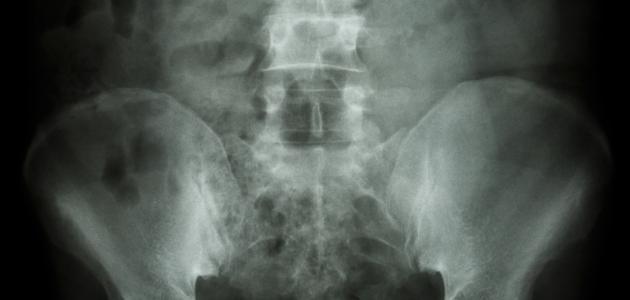

يُعتبر الكالسيوم أحد العناصر المُهمّة في جسم الإنسان، إذ إنّ ما نسبته 99% من الكالسيوم الذي يدخل الجسم ينتهي به المطاف مترسّباً في العظام والأسنان، أمّا النسبة المُتبقية فتبقى ذائبة في الدم، وقد يتعرّض الجسم لاضطراب مُعين يُخلّ بالتوازن ما بين الكالسيوم وعدد من العناصر الكيميائيّة المحدّدة في الجسم؛ ممّا قد ينتج عنه ترسّب الكالسيوم في أجزاء مختلفة من الجسم؛ بما في ذلك الشرايين، والكلى، والرئتين، والدماغ، ويُمكن تعريف التكلّس (بالإنجليزية: Calcification) على أنّه تراكم الكالسيوم بشكلٍ تدريجيّ في أنسجة الجسم، ممّا يؤدّي إلى تصلّبها، وقد تكون هذه العملية طبيعية أو غير طبيعية، وفي الحقيقة يُعتبر التكلّس مشكلة صحيّة في حال أثّر التكلّس في وظيفة أحد الأعضاء الحيويّة في الجسم، وفي بعض الأحيان قد يحدث اضطراب في مستوى الكالسيوم في الدم؛ ممّا يُشير إلى وجود اضطراب أيضيّ تتأثر فيه قدرة الجسم على استخدام الكالسيوم أو تنظيم مستوياته.[١][٢]